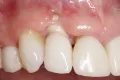

Профилактика потери зубного сосочка и развития рецессии в периимплантатной области

Удовлетворительные долгосрочные показатели выживаемости эндоосальных имплантатов аргументируют распространённость их использования в стоматологической практике с целью максимальной реабилитации пациента. Однако, несмотря на это формирование необходимого эстетического профиля во фронтальном участке с использованием протетических конструкций, опирающихся на титановые опоры, использование данного метода является довольно проблематичным и не всегда предсказуемым. Наиболее часто среди осложнений случаются потери межзубных сосочков и серединные рецессии. Частота подобных осложнений составляет около 7,1% в 5-летней ретроспективе. Kan и коллеги сообщили, что суммарный показатель успешности имплантатов при реализации протокола немедленной установки составляет 100% в ходе 4-летнего мониторинга, тем не менее, развитие рецессий все равно наблюдается через 1 год функционирования имплантатов с частотой компрометации эстетического профиля в 11% случаев. Исходя из этого, можно резюмировать, что, несмотря на высокую успешность имплантатов, осложнения в области периимплантатных мягких тканей являются довольно распространёнными, что, в конечном счете, приводит к неудовлетворительному функционально-эстетическому результату стоматологической реабилитации пациента.